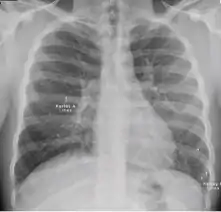

Chest X-ray of a person with advanced tuberculosis: Infection in both lungs is marked by white arrow-heads, and the formation of a cavity is marked by black arrows.

3. Nodule with poorly defined margins - Round density within the lung parenchyma, also called a tuberculoma. Nodules included in this category are those with margins that are indistinct or poorly defined (tree-in-bud sign[3]). The surrounding haziness can be either subtle or readily apparent and suggests coexisting airspace consolidation.

Chest x-ray showing nodule with margins that are indistinct or poorly defined (tree-in-bud sign) in post-primary pulmonary TB.